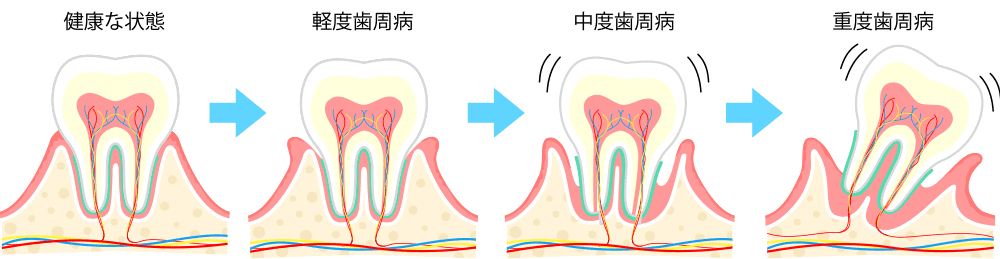

歯周病の進行状況

健康な歯肉には、ステップリング (みかんの皮の表面の小さなくぼみのような状態)がみられます。

| 写真右:サンゴ色、またはピンク色で ひきしまって弾力性のある健康歯肉 |  |

| 歯のつけ根の表面に、プラークがたまり、 歯の周囲や歯と歯の間の歯肉に炎症が起こります。 ブラッシングした時や、固いものを食べると、 出血することがあります。これくらいではまだ痛みもありません。 (この段階を「歯肉炎」といいます) 写真右:歯肉炎 |  |

| プラークが歯石になり、歯石は大きくなって、 歯と歯槽骨をつなぐ歯根膜が破壊され、歯周ポケットが形成されます。 歯周ポケットはだんだん深くなり、歯肉の弾力性が なくなって、 炎症も進んで、 歯槽骨の破壊も始まります。歯と歯の間に隙間ができています。 写真右:歯周炎 |  |

| 症状が進むと歯周ポケットがさらに深くなり、 歯槽骨が破壊され、歯がぐらつき歯の根も見えてきます。 出血や口臭も強くなり常時ウミが出るようになります。 歯のぐらつきが大きくなると抜歯に至ります。この状態になると次々と歯がなくなります。 写真右:重度歯周炎 |  |